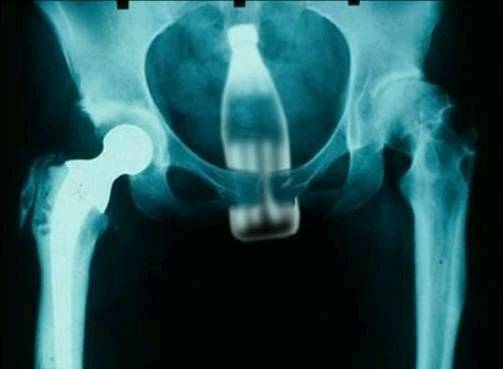

Other rectal FB